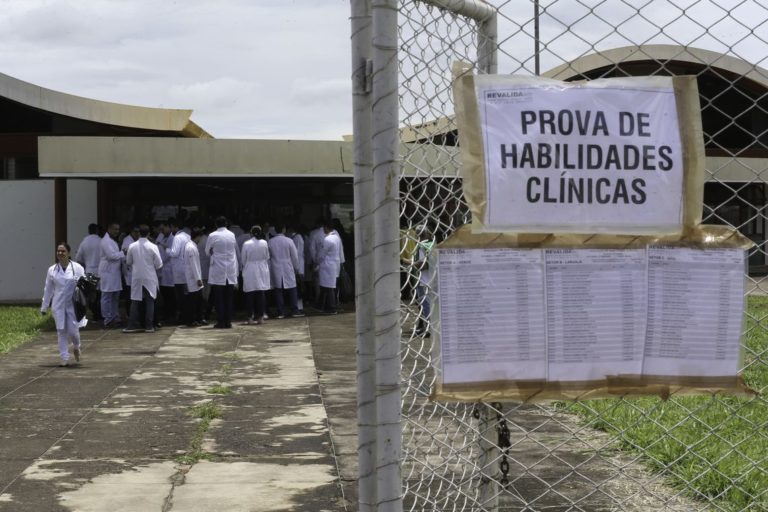

Acreanos formados no exterior interessados em participar do Exame Nacional de Revalidação de Diplomas Médicos Expedidos por Instituição de Educação Superior Estrangeira (Revalida) 2020 têm

Acreanos formados no exterior interessados em participar do Exame Nacional de Revalidação de Diplomas Médicos Expedidos por Instituição de Educação Superior Estrangeira (Revalida) 2020 têm